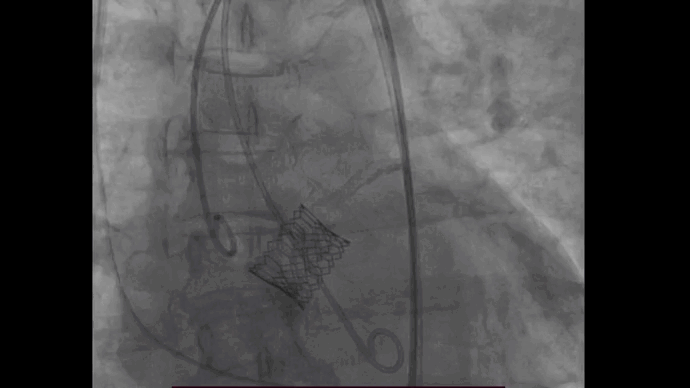

图片

推送